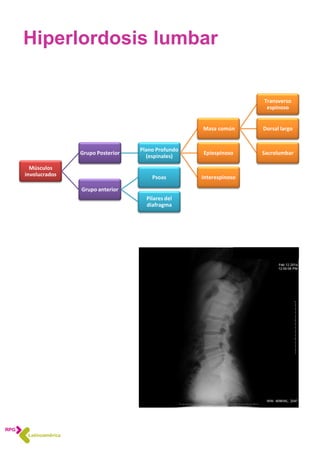

Hiperlordosis lumbar

Músculos

involucrados

Grupo Posterior

Plano Profundo

(espinales)

Masa común

Transverso

espinoso

Dorsal largo

SacrolumbarEpiespinoso

Interespinoso

Grupo anterior

Psoas

Pilares del

diafragma